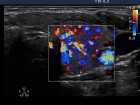

First examination (first row):

Ultrasonography: Both lobes were enlarged, moderately hypoechogenic, inhomogeneous and displayed increased vascularization.

2. Note the relation between volume, echogenicity, vascularization and hormone levels.